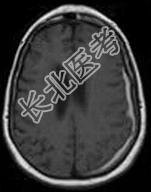

- 单项选择题女,71岁, 头晕,言语模糊, 2周前被摩托车撞伤,结合MRI图像选择最可能的诊断 ( )

D、亚急性硬膜下血肿

E、慢性硬膜下血肿